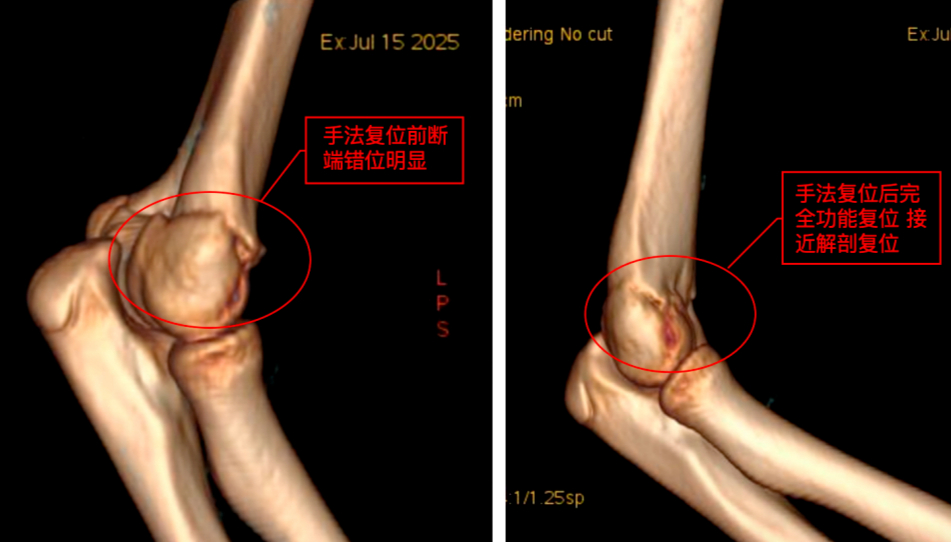

她赶紧带着孩子赶到医院,拍片、诊断、复位、固定,整个诊疗过程迅速又专业。主诊医生的精湛操作让孩子免于手术创伤,医护人员的人文关怀更令李女士动容。